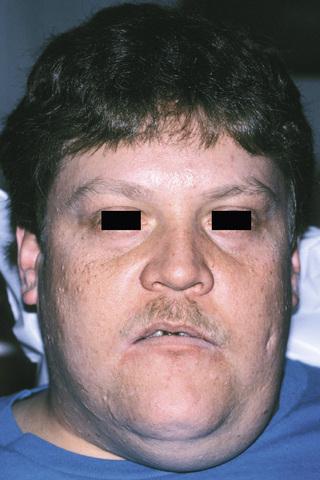

sialadenosis

Enlargement of the parotid and submandibular glands secondary to alcoholism. Sialography demonstrates a “leafless tree” pattern.

sialadenosis